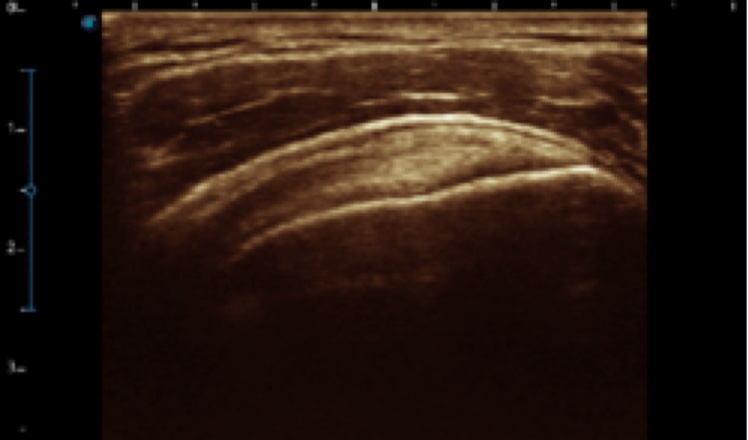

X5采用前端的超声专用芯片,将台式机大规模集成电路完美压缩在笔记本超声的精巧下,提高了系统的运算速度,加载μ-Scan微米成像、脉冲反相谐波等技术,带来优异的临床表现,清晰呈现高分辨率二维图像和层次丰富的血流图像

X5具备实时宽景成像、穿刺增强、彩色M型、组织多普勒等多种高级成像功能,全方位满足多个科室的诊断需求,整机系统向智能化跨越